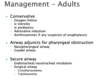

URGENT: Post tonsillectomy bleed, Laryngectomy issues, Unstable epistaxis, Stridor (airway compromise)

SOON (30 MINS): Periorbital cellulitis, Foreign body, Stable epistaxis, Quinsy

ADVICE: OE/OM, Bell’s Palsy, Acute sensorineural hearing loss, Acute vestibulopathy